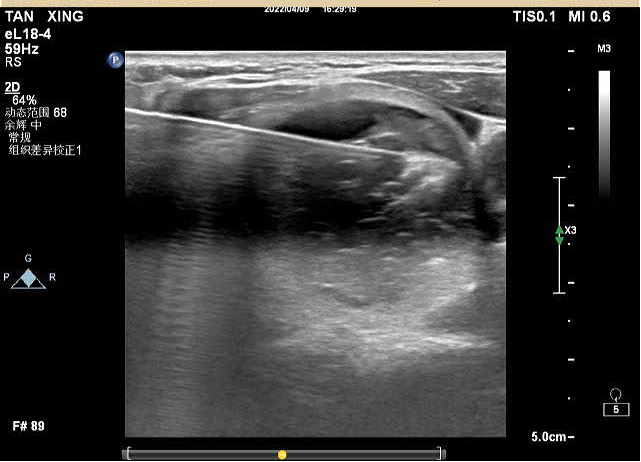

對結(jié)節(jié)的囊性部分進行穿刺抽吸+聚桂醇反復(fù)沖洗

對結(jié)節(jié)實性部分進行移動式+固定式射頻消融